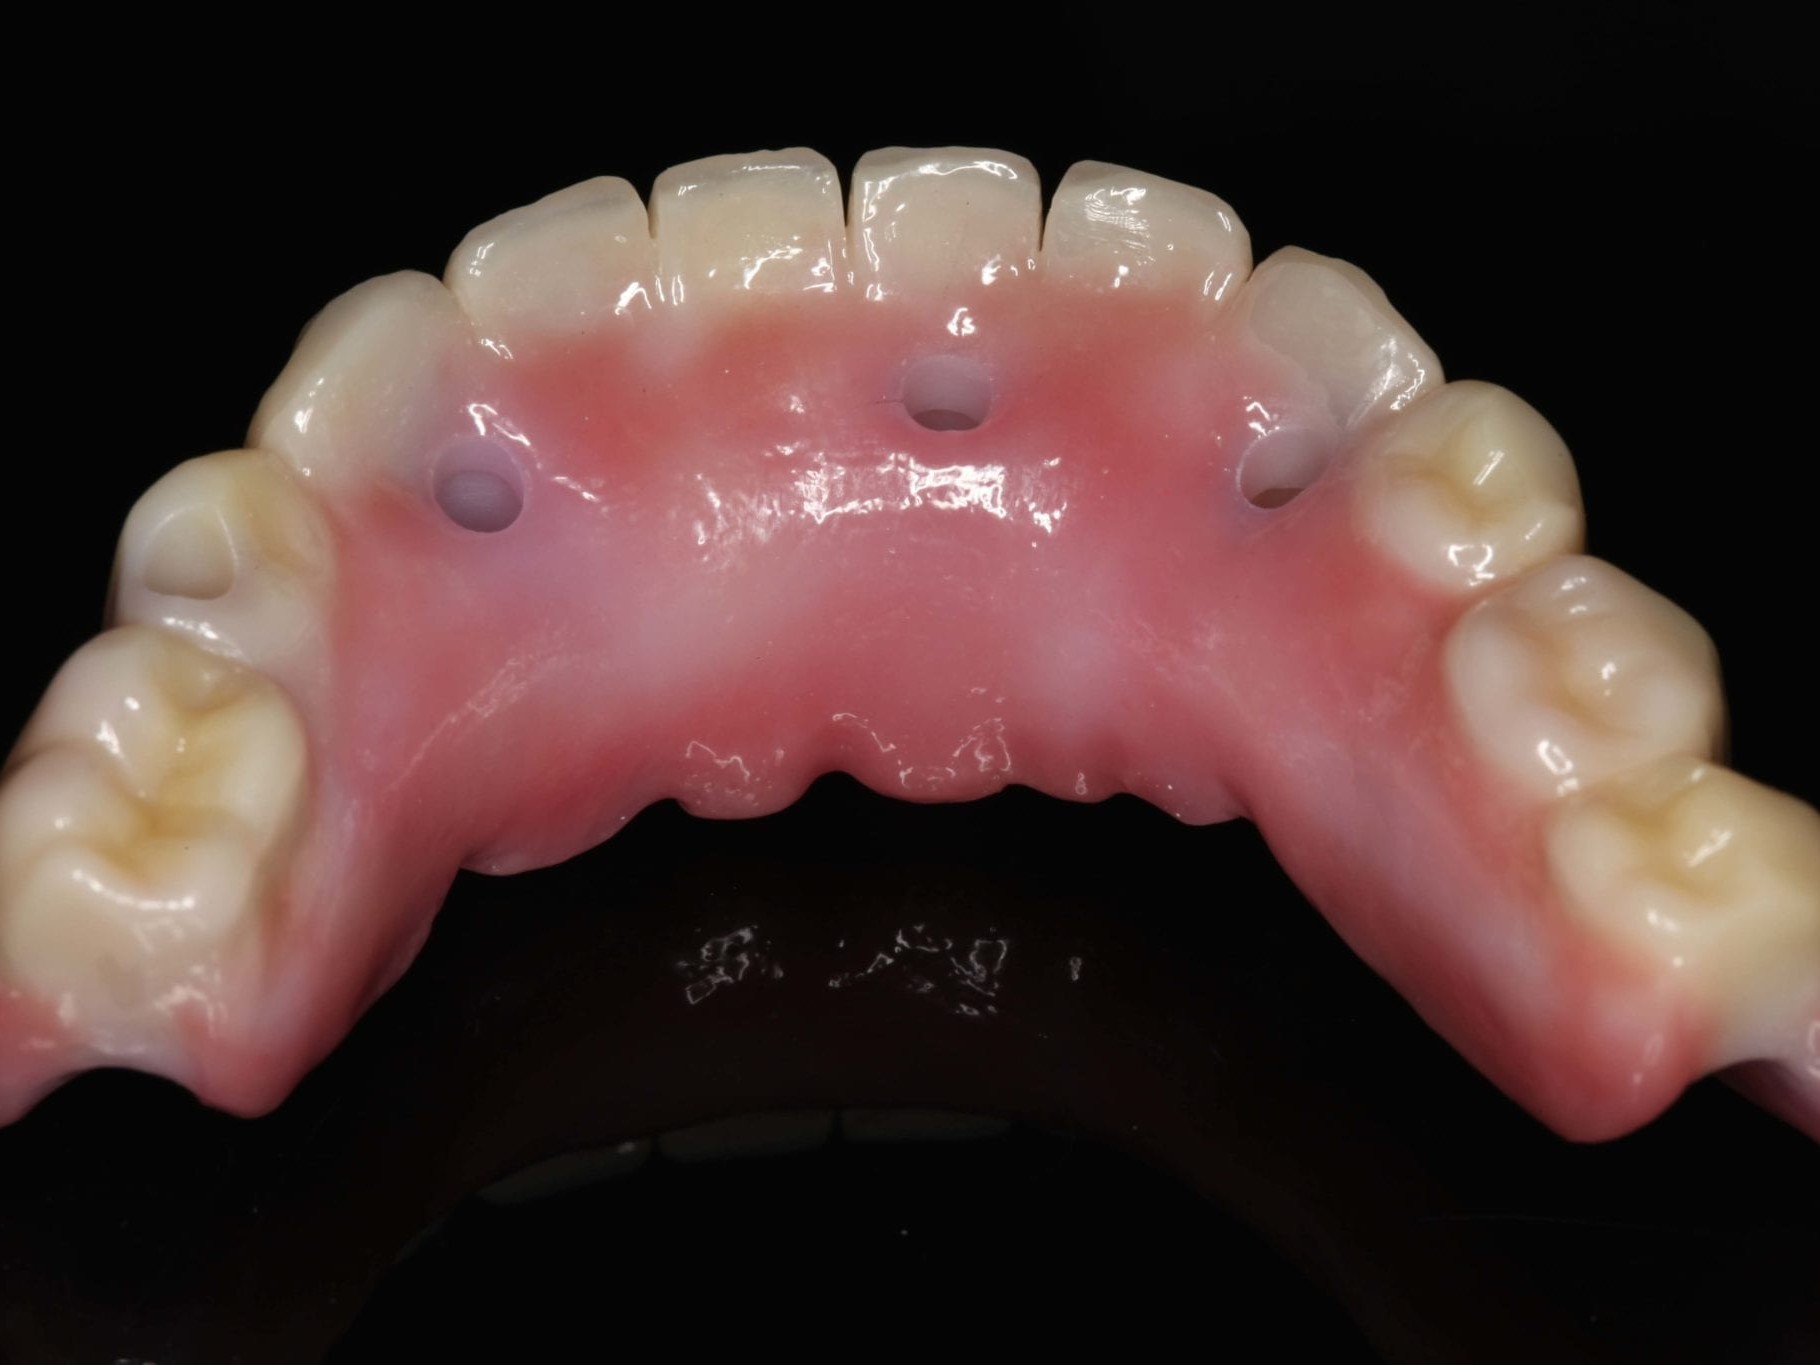

Nach erneuter Überprüfung der implantatprothetischen Sofortversorgung auf sämtliche okklusalen und gelenkspezifischen Parameter erfolgte die Abformung im Ober- und Unterkiefer (Abb. 22). Da die Ankylos Balance-Basis Aufbauten intraoperativ bereits zum Zeitpunkt der Interimsversorgung definitiv eingesetzt wurden, erfolgte die Abformung auf Abutmentniveau mit einem Folienlöffel für präzise Implantatabformung. Um die visuelle Kontrolle über den Abformprozesses zu haben, kam ein transparentes Abformmaterial zur Anwendung. Zur präzisen Übertragung der Mundsituation auf das Modell ist entweder eine zweite Abformung mit einem entsprechenden laborgefertigten Kontrollschlüsssel oder eine direkte intraorale Verblockung der Ankylos Abformpfosten erforderlich¹¹. Bei der letztgenannten Variante werden die direkte Verblockung der Abformpfosten und die präzise Implantatabformung miteinander kombiniert (Abb. 23). Hierfür wird Zahnseide spannungsfrei mehrfach über Kreuz um die Abformpfosten geschlungen. Das hieraus entstehende Gerüst dient als Trägerplattform für das Autopolymerisat, das wir in Pinseltechnik appliziert haben. Um ein zügigeres Arbeiten am Patienten zu gewährleisten, kamen vorgefertigte Stangen (Ø 3 mm) aus rotem Modellierkunststoff zum Einsatz. Dieser Modellierkunststoff zeigt auch bei sehr dünnen Schichtstärken eine minimale Schrumpfung bei hoher Festigkeit sowie Stabilität. Das zeitversetzte Applizieren des Autopolymerisates gewährleistet die Spannungsfreiheit der Verblockung. Das Meistermodell wurde aus Klasse–IV-Superhartgips mit typischer Gingivamaske hergestellt. Bei weitspannigen Suprastrukturen lässt sich die höchste Genauigkeit mit einer verblockten Präzisionsabformung erreichen. Die durch das nach distal ausgedehnte prothetische Polygon bedingte Weitspannigkeit ist das Prinzip des SmartFix-Konzeptes. Nach der Modellherstellung erfolgte die anatomisch korrekte Übertragung der Schädel-Achs-Relation des Oberkiefers in den Artikulator mittels Gesichtsbogen. Zur Montage des Unterkiefers konnte in diesem Fall auf eine klassische Bissnahme verzichtet werden, da das computerdesignte und okklusal verschraubte Langzeitprovisorium während der Einheilphase vom Behandler feinjustiert wurde und somit die Bisshöhe und -lage zur Übertragung perfekt geeignet war. Hierfür wurde das Provisorium entnommen, so dass der Zahntechniker die Artikulation und die damit verbundene Individualisierung der Artikulatorenwerte in der Praxis vornehmen konnte. Im Labor erfolgte die komplette Digitalisierung des Falles. Der gesamte Workflow dieses Patientenfalles beruht auf dem Prinzip des Backward Plannings. Dem Team, bestehend aus einem implantatchirurgischen und einem implantatprothetischen Behandler sowie einem Zahntechniker, ist daran gelegen, sowohl chirurgisch als auch prothetisch vorhersagbare Ergebnisse zu generieren. Bei einer okklusal verschraubten Brücke ist es für den Zahntechniker vor Beginn der Arbeit wichtig, den späteren Austrittspunkt der Schraubenkanäle zu kennen und eine diagnostische Aufstellung in Form und Funktion anzufertigen. Nur so wird gewährleistet, dass das CAD/CAM gefertigte Gerüst die Verblendungen optimal unterstützt und die Schraubenkanäle ideale Durchtrittspunkte bekommen. Durch das im Vorfeld erstellte digitale Sofortprovisorium konnte die ästhetische Ausgangssituation der Patientin sowie die individuellen Okklusionsparameter bis hierhin fehlerfrei übernommen werden. Dieses Sofortprovisorium wurde mittels Alginat in situ abgeformt und nach der Modellherstellung digitalisiert. Zur Steigerung der Präzision wurde darüber hinaus ein klassisches diagnostisches Wax-Up erstellt, das den Verlauf der rot-weißen Ästhetik wiedergab. Diese Datensätze wurden dann mit den Scandaten des Meistermodells in einem CAD Programm gematcht (Abb. 24). Damit standen dem Zahntechniker alle benötigten Informationen zur Erarbeitung eines Designvorschlages für das anatomisch teilreduzierte Brückengerüst aus Zirkondioxid zur Verfügung. Die auf den Zehntelmillimeter genau festzulegende Reduktion des Gerüstes richtet sich nach der Indikation der Verblendung. Wie weiter oben bereits beschrieben, ist die Patientin im Oberkiefer mit einer herausnehmbaren Kunststofftotalprothese versorgt. Aus Sicht des Behandlungsteams war dadurch eine keramische Verblendung des Unterkiefers möglich. Aus Stabilitätsgründen entschied sich das Team für eine Versorgung aus monolithischem Zirkondioxid, das zur Steigerung der Ästhetik von 033 bis 043 vestibulär verblendet wurde (Abb. 25). Die Verwendung von monolithischem Zirkon in Verbindung mit einer keramischen Teilverblendung gewährleistet neben der notwendigen Ästhetik und Stabilität zwei weitere Vorteile. Auf der einen Seite zählt Zirkondioxid in der Zahnheilkunde zu den Materialien mit der höchsten Biokompatibilität und zum anderen werden die auftretenden Kaukräfte gerade in Verbindung mit der Versorgung im Oberkiefer gleichmäßiger auf das Implantat und den Knochen verteilt. Gerade bei implantologischen Oberkiefer- und Unterkieferversorgungen ist dieser „Stoßdämpfer–Effekt“ für den Langzeiterfolg wichtig. Im vorliegenden Fall wurde die okklusal verschraubte Brücke mit einem Sintergerüst versehen und mit einer fünfachsigen Fräsmaschine im Labor aus einem Zirkonblock gefräst. Bevor das Gerüst mit einem speziell entwickelten Langzeitprogramm gesintert wurde, erfolgte die individuelle Einfärbung des Zirkondioxides mit Color Liquids. Die anschließende vestibuläre Verblendung der Zähne und des Zahnfleisches wurde unter Zuhilfenahme der diagnostischen Aufstellung mit Verblendkeramik angefertigt. Hierbei wurde besonderer Wert auf die naturgetreue Nachbildung der Rot-WeißÄsthetik und eine gute Hygienefähigkeit geachtet. Die gefertigte Arbeit wurde mit einem dafür zugelassenen Kleber auf die Ankylos Stegkappen (für Balance Basisaufbau schmal, aus Permador® PDF, Dentsply Implants) verklebt, die zuvor auf dem Meistermodel aufgeschraubt worden waren. In Übereinstimmung mit den als Sheffield-Test¹² bekannten Kriterien der University of Sheffield, GB, ermöglicht dieser Fertigungsprozess in Kombination mit der verblockten Abdrucknahme einen präzisen und somit spannungsfreien Sitz der Brücke – sowohl auf dem Meistermodell als auch im Munde des Patienten (Abb. 26 bis 28). Nach der zahntechnischen Fertigstellung der Unterkieferbrücke wurde diese intraoral inkorporiert (Abb. 29 und 30). Die Ankylos Implantatschrauben wurden mit 25 Ncm angezogen. Wichtig ist, dass stets das Originalequipment des Herstellers oder ein elektronisch kalibrierter Schraubendreher verwendet wird. Die Schraubenkamine wurden mit einem bakteriendichten, formstabilen lichthärtenden Füllungsmaterial verschlossen. Nach 6 Wochen wurde ein abschließendes OPG erstellt (Abb. 31).